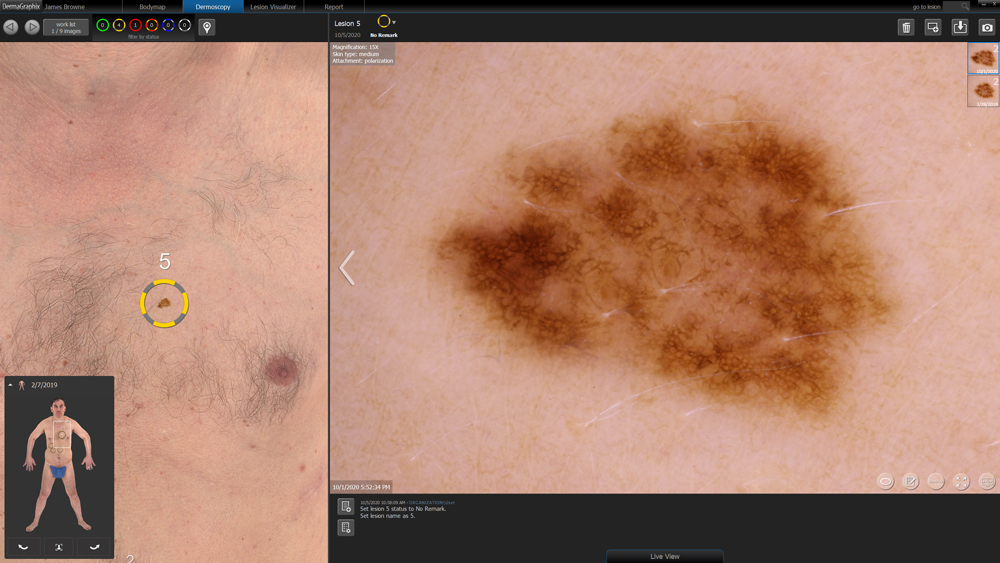

Designed specifically for dermatology, the VECTRA WB360 whole body 3D imaging system captures the entire skin surface in macro quality resolution with a single capture. The fully integrated software allows clinicians to map and monitor pigmented lesions and distributed diseases of the skin. Other applications include documenting psoriasis and vitiligo.